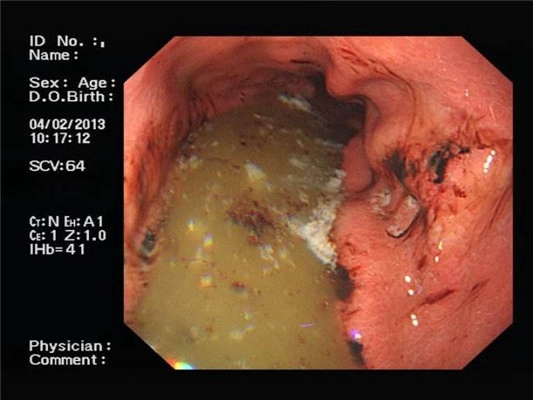

食道炎圖片